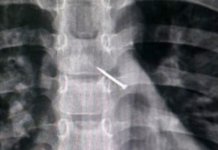

Новосибирские медики извлекли из бронхов ребенка канцелярскую кнопку

В новосибирскую детскую клиническую больницу скорой медицинской помощи поступил 9-летний мальчик, родители которого сообщили, что во время игры их сын случайно вдохнул канцелярскую кнопку...